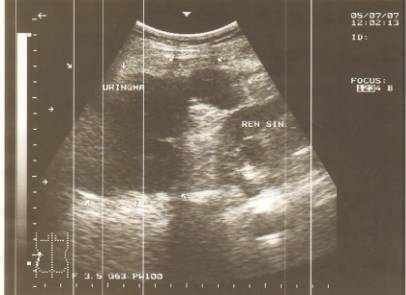

контурів та їхня переривчатість. В перші 6 годин після травмування гематоми

характеризувалися наявністю ділянок підвищеної ехогенності з розмитими,

нерівними контурами (стадія травматичної інфільтрації), що наведено на рисунку

1.

Рис. 1. Гостре рідинне скупчення в

паранефральній клітковині зліва в перші 6 годин після травми. В-режим.